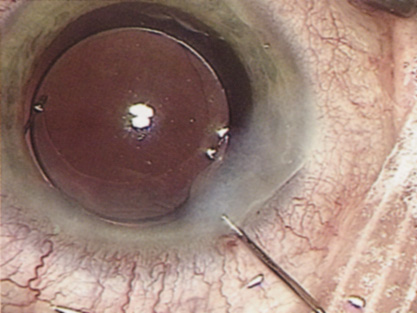

At the turn of the century, the incidence of posterior capsular opacification (PCO), the most common untoward event after surgery, was plummeting as the result of a square edge design on the IOL optic. The haptics themselves had evolved from Prolene material to polymethylmethacrylate and then Alcon introduced a soft haptic on a single-piece acrylic platform. Every company developed an injector for improved IOL insertion, and industry was teaming up with innovative surgeons in developing a number of optic modifications. Attempts to achieve multifocality with diffractive optics had been introduced by 3M and their design team of Richard Lindstrom, John Sheets, and Robert Osher. This technology was placed on the back burner until Allergan developed the array multifocal IOL. Alcon purchased and improved the 3M defractive optic and introduced ReStor IOL on a single-piece acrylic platform. The surgical assault on presbyopia accelerated as Eyeonics developed the Crystalens, the first IOL with a pliable optic aimed at generating accommodation, a concept introduced a decade before by Spencer Thornton.33 A toric optic was developed by Staar Surgical; Pharmacia introduced Tecnis, the first spherical aberration-correcting IOL; and Alcon developed the first blue-light–filtering optic to provide macular protection. The once narrowly defined specialty of cataract and IOL surgery was exploding with new ideas and technologies. Smaller-incision IOLs were being designed that could be injected through <2-mm incisions. A host of surgeons, including Amar Agarwal, Jorge Alio, Richard Packard, Hiroshi Tsuneoka, Virgilio Centurion, Howard Fine, and Randy Olson, were exploring microincisional cataract surgery through 1.5-mm incisions by separating the sleeveless ultrasound tip from the irrigating chopper.

Refractive lens replacement and phakic implantation also were gradually earning a rightful place in anterior segment surgery. In the early 1980s, Franco Verzella from Italy initially removed the clear lens for extreme myopia, but surgeons were concerned about the incidence of retinal detachment in this group of high-risk eyes. Robert Osher performed the first clear lensectomy for hyperopia in 1985 and although the risk of retinal detachment was lower, these eyes were challenging both in surgery and in accurately selecting the IOL.34,35 John Gayton's novel approach of using “piggyback” IOLs met with enthusiasm until interlenticular opacification emerged.36 AcriTec engineers from Germany identified a method of manufacturing lens power up to +60 diopters. Phakic implantation with IOLs fixated in the anterior chamber (Baikoff, Kelman, Choyce) and the posterior chamber (Fyodorov, Adatomed, PRL, Staar Surgical) were being developed. The iris-supported Verisyse (Artisan developed by Jan Worst) became the first phakic IOL approved in the United States.